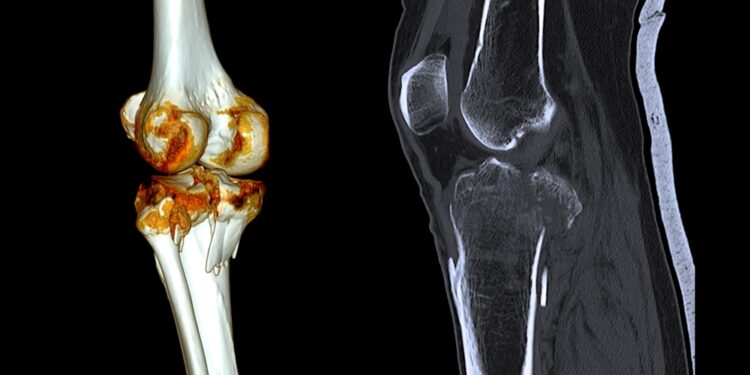

Tikslesniam lūžio pobūdžio įvertinimui dažniausiai atliekami rentgeno tyrimai, sudėtingesniais atvejais – kompiuterinė tomografija.